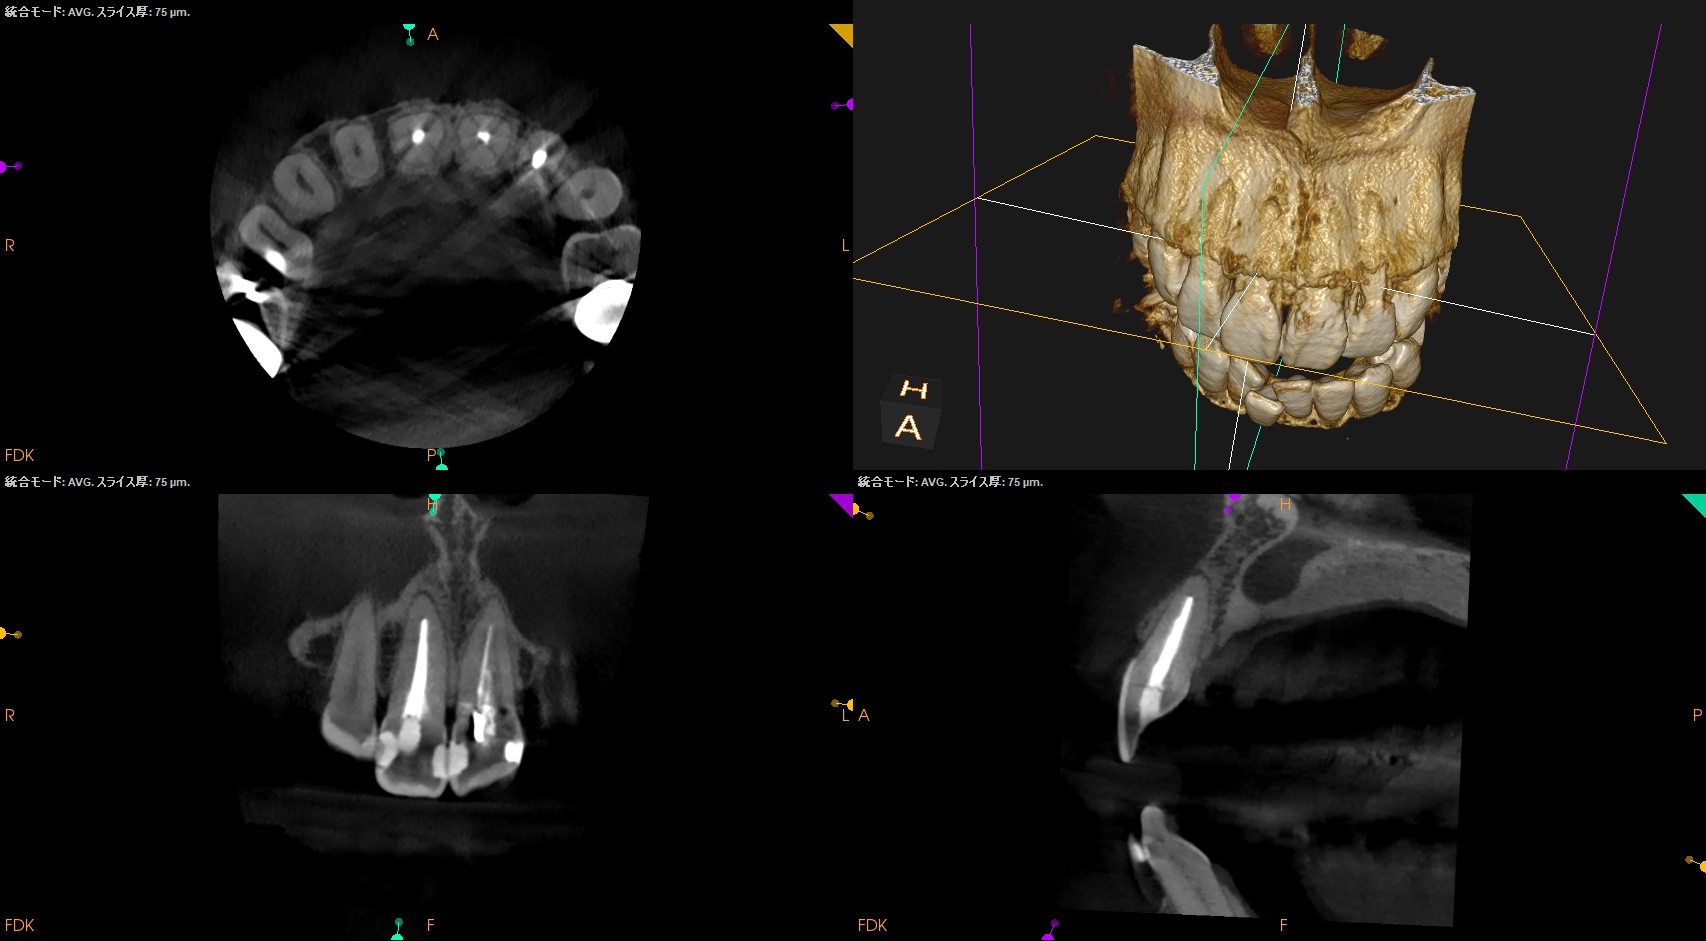

CBCT(2025.6.3)

#8はApexが歯槽骨からはみ出ている。

PA所見から考察するに、再治療よりも外科治療だろう。

#8 Apicoectomy 6M recall(2025.12.2)

PA, CBCTを撮影した。

初診時と比較した。

劇的に状況は改善している。

#8,9,10に最終補綴もOKだろう。